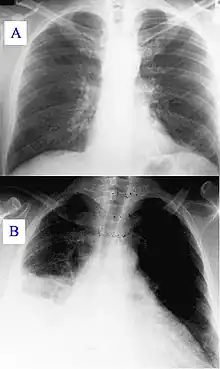

| A) Normal chest radiograph; B) Q fever pneumonia affecting the right lower and middle lobes. Note the loss of the normal radiographic silhouette (contour) between the affected lung and its right heart border as well as between the affected lung and its right diaphragm border. This phenomenon is called the silhouette sign | |

In radiology, the silhouette sign refers to the loss of normal borders between thoracic structures.[1] It is usually caused by an intrathoracic radiopaque mass that touches the border of the heart or aorta.[2] In other words, it is difficult to make out the borders of a particular structure - normal or otherwise - because it is next to another dense structure, both of which will appear white on a standard X-ray.[3] It may occur, for example, in right middle lobe syndrome, where the right heart margin is obscured, and in right lower lobe pneumonia, where the border of the diaphragm on the right side is obscured, while the right heart margin remains distinct.[2] Silhouette sign is very useful in localizing lung lesions as all structures forming cardiac silhouette are in contact with a specific portion of the lung.